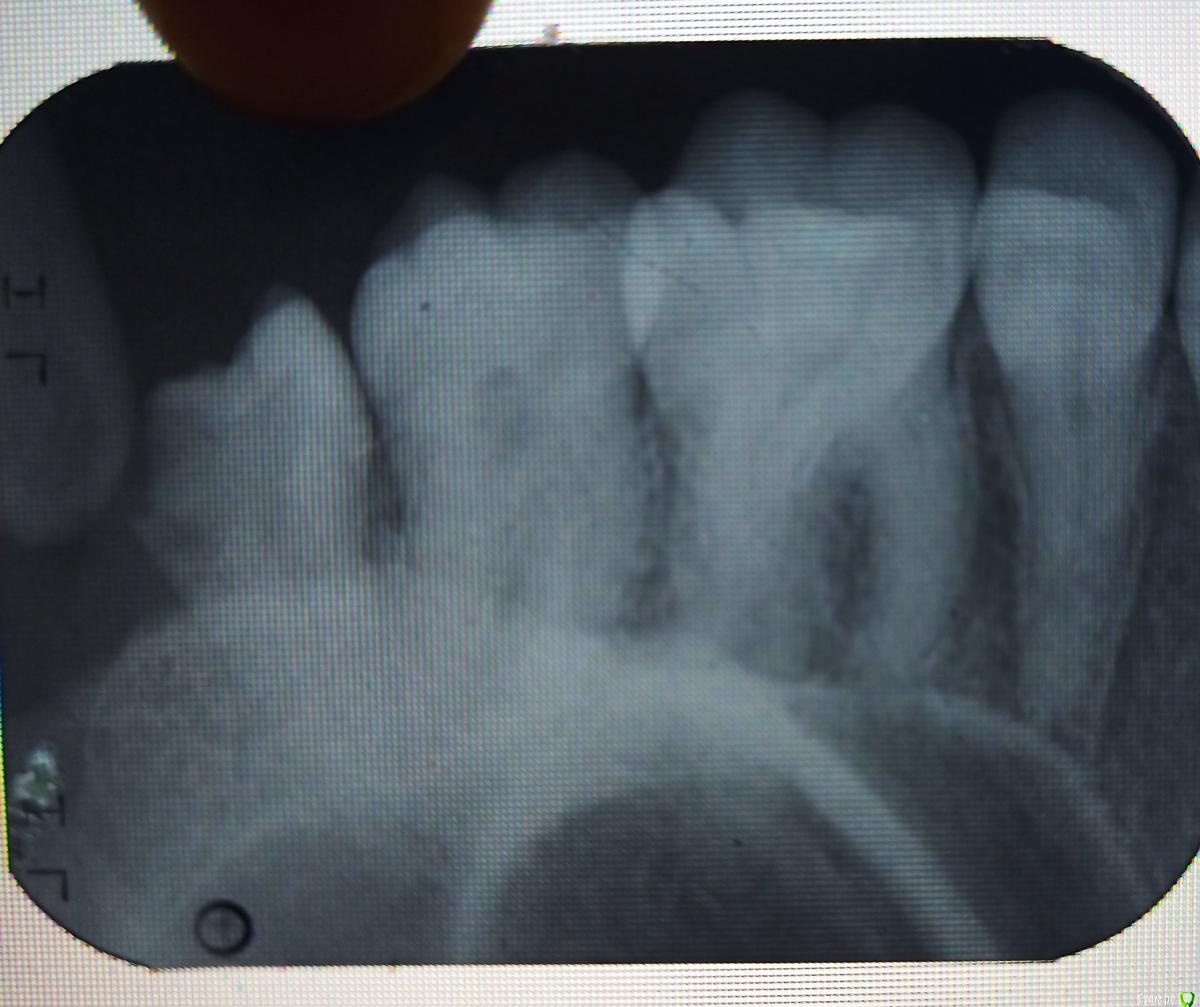

Mudrets Опубликовано 17 марта, 2021 Автор Поделиться Опубликовано 17 марта, 2021 Вот снимок Ссылка на комментарий

shishok Опубликовано 17 марта, 2021 Поделиться Опубликовано 17 марта, 2021 Если Вы имеете ввиду зуб мудрости,то удалять. 2 Ссылка на комментарий

Mudrets Опубликовано 17 марта, 2021 Автор Поделиться Опубликовано 17 марта, 2021 В общем подруга ходила в поликлинику, ей сказали что-то там подгнило, кариес. Про зуб мудрости ни слова. Прошу помочь советом, а то боюсь удалят, что не надо 1 Ссылка на комментарий

chervoncevdaniil Опубликовано 18 марта, 2021 Поделиться Опубликовано 18 марта, 2021 Речь о зубе мудрости,удалять 1 Ссылка на комментарий